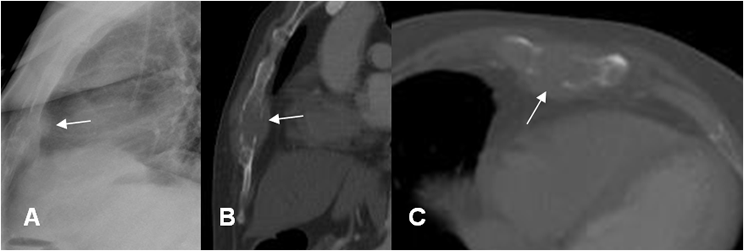

Fig 39 A. Mesotelioma.

A: Rx PA. Imagen de localización extra-pleural, en el tercio superior del hemitórax izquierdo.

B: TAC axial, C: TAC reconstrucción coronal y D: TAC reconstrucción sagital. Imagen de contornos bien definidos y lobulados.

Fig 39 B. Mesotelioma.

A: RM axial en T2, B: RM axial en T1 simple y C: RM axial en T1 con contraste. Igual paciente anterior. Imagen de ubicación extrapleural, hipointensa en ambas secuencias por su contenido fibroso y que realza de forma heterogénea con el contraste, correspondiendo a mesotelioma.